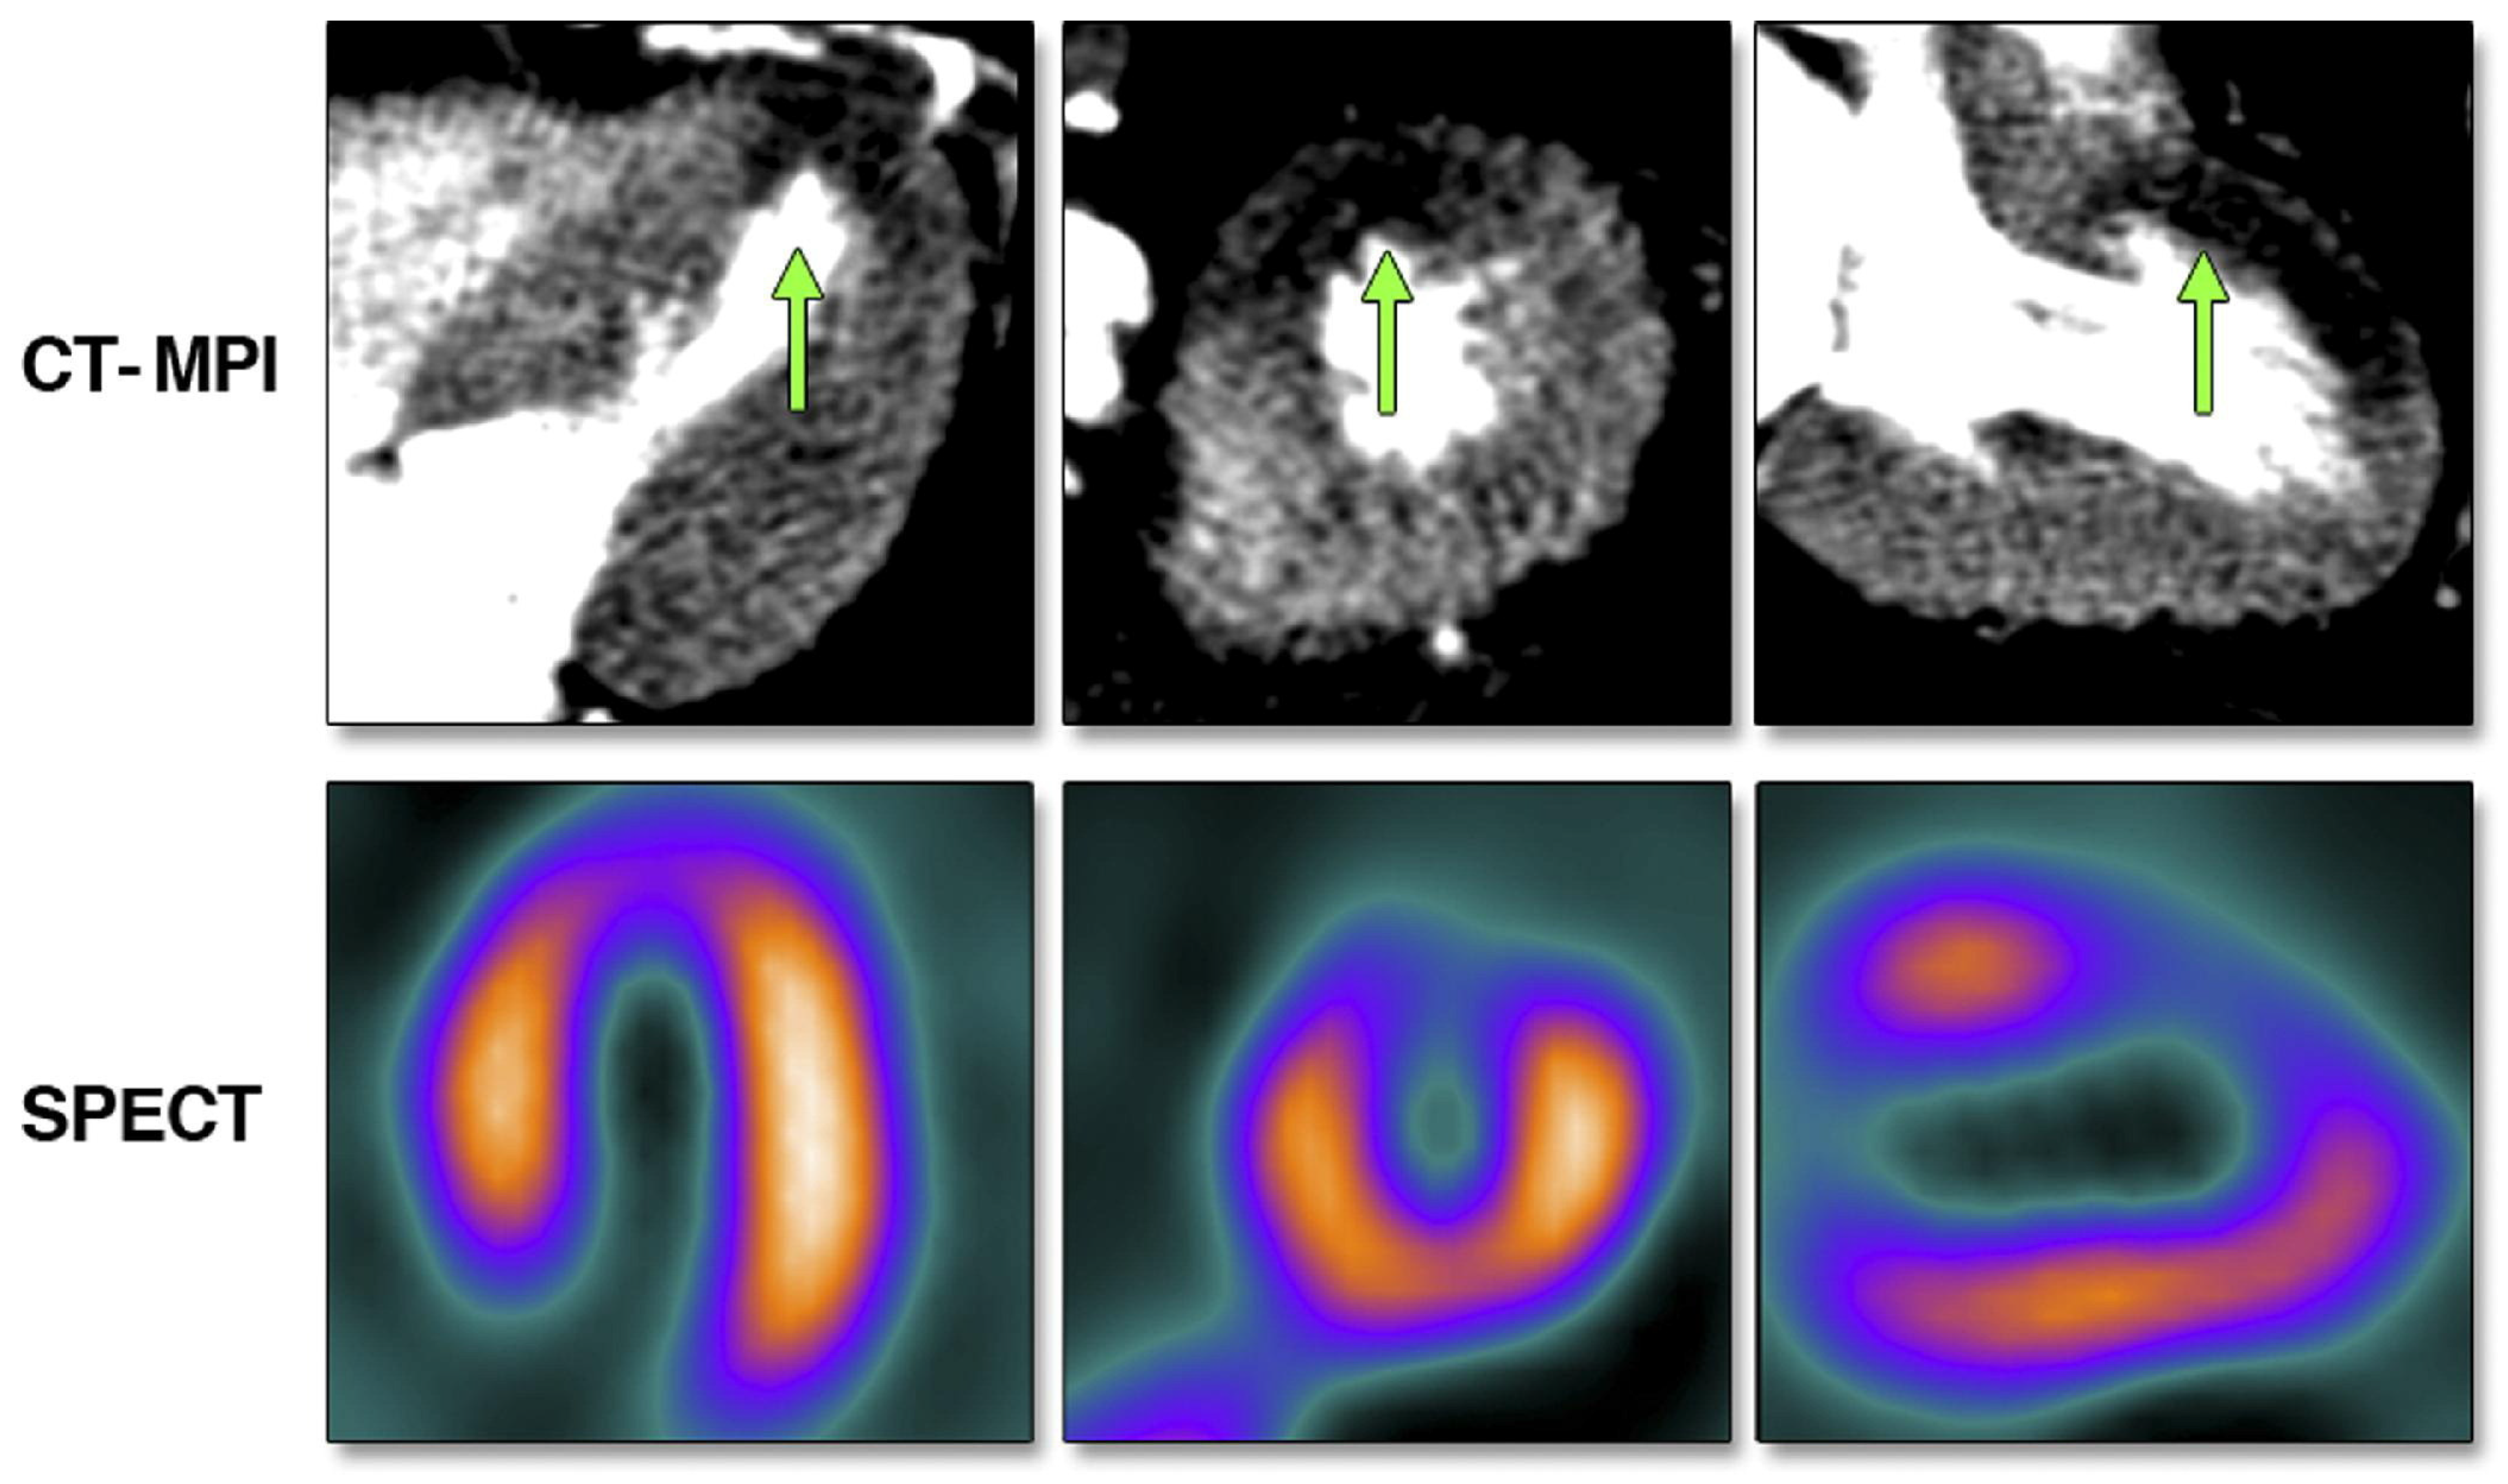

Figure 5.

Stress perfusion defect, indicated by the green arrows, in the mid- and distal anterior wall during adenosine stress computed tomography-myocardial perfusion imaging (top) and the perfusion defect in the same wall segments using single photon emission tomography-myocardial perfusion imaging (bottom). Reprinted from JACC: Cardiovascular Imaging, Volume 3, Issue 10, Tamarappoo, B.K. et al. [177], Comparison of the Extent and Severity of Myocardial Perfusion Defects Measured by CT Coronary Angiography and SPECT Myocardial Perfusion Imaging, pages 1010–1019, Copyright 2010, with permission from Elsevier.